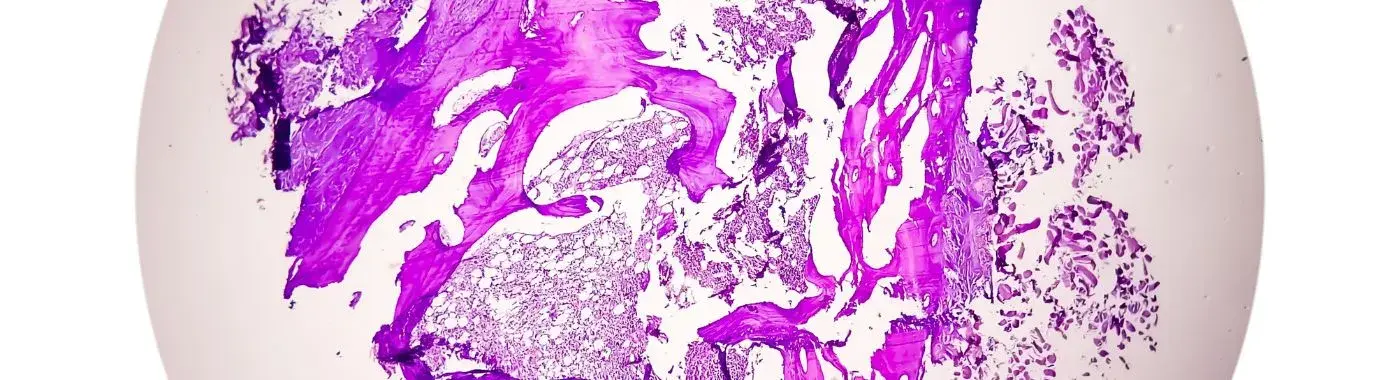

Thyroglossal duct cysts (TGDCs) are the most common type of congenital neck mass found in children, although they can also occur in adults. These cysts arise from remnants of the thyroglossal duct, a structure that forms during the development of the thyroid gland. Understanding thyroglossal duct cysts is significant not only for their prevalence but also for their potential complications if left untreated. This article aims to provide a comprehensive overview of thyroglossal duct cysts, including their definition, causes, symptoms, diagnosis, treatment options, complications, prevention strategies, prognosis, and frequently asked questions.

Thyroglossal duct cysts are fluid-filled sacs that develop in the midline of the neck, typically just below the hyoid bone. They are formed from remnants of the thyroglossal duct, which is a temporary structure that connects the developing thyroid gland to the base of the tongue during fetal development. Normally, this duct disappears as the thyroid gland descends into its final position in the neck. However, if parts of the duct remain, they can form a cyst, which may become noticeable at any age, although they are most commonly diagnosed in children.